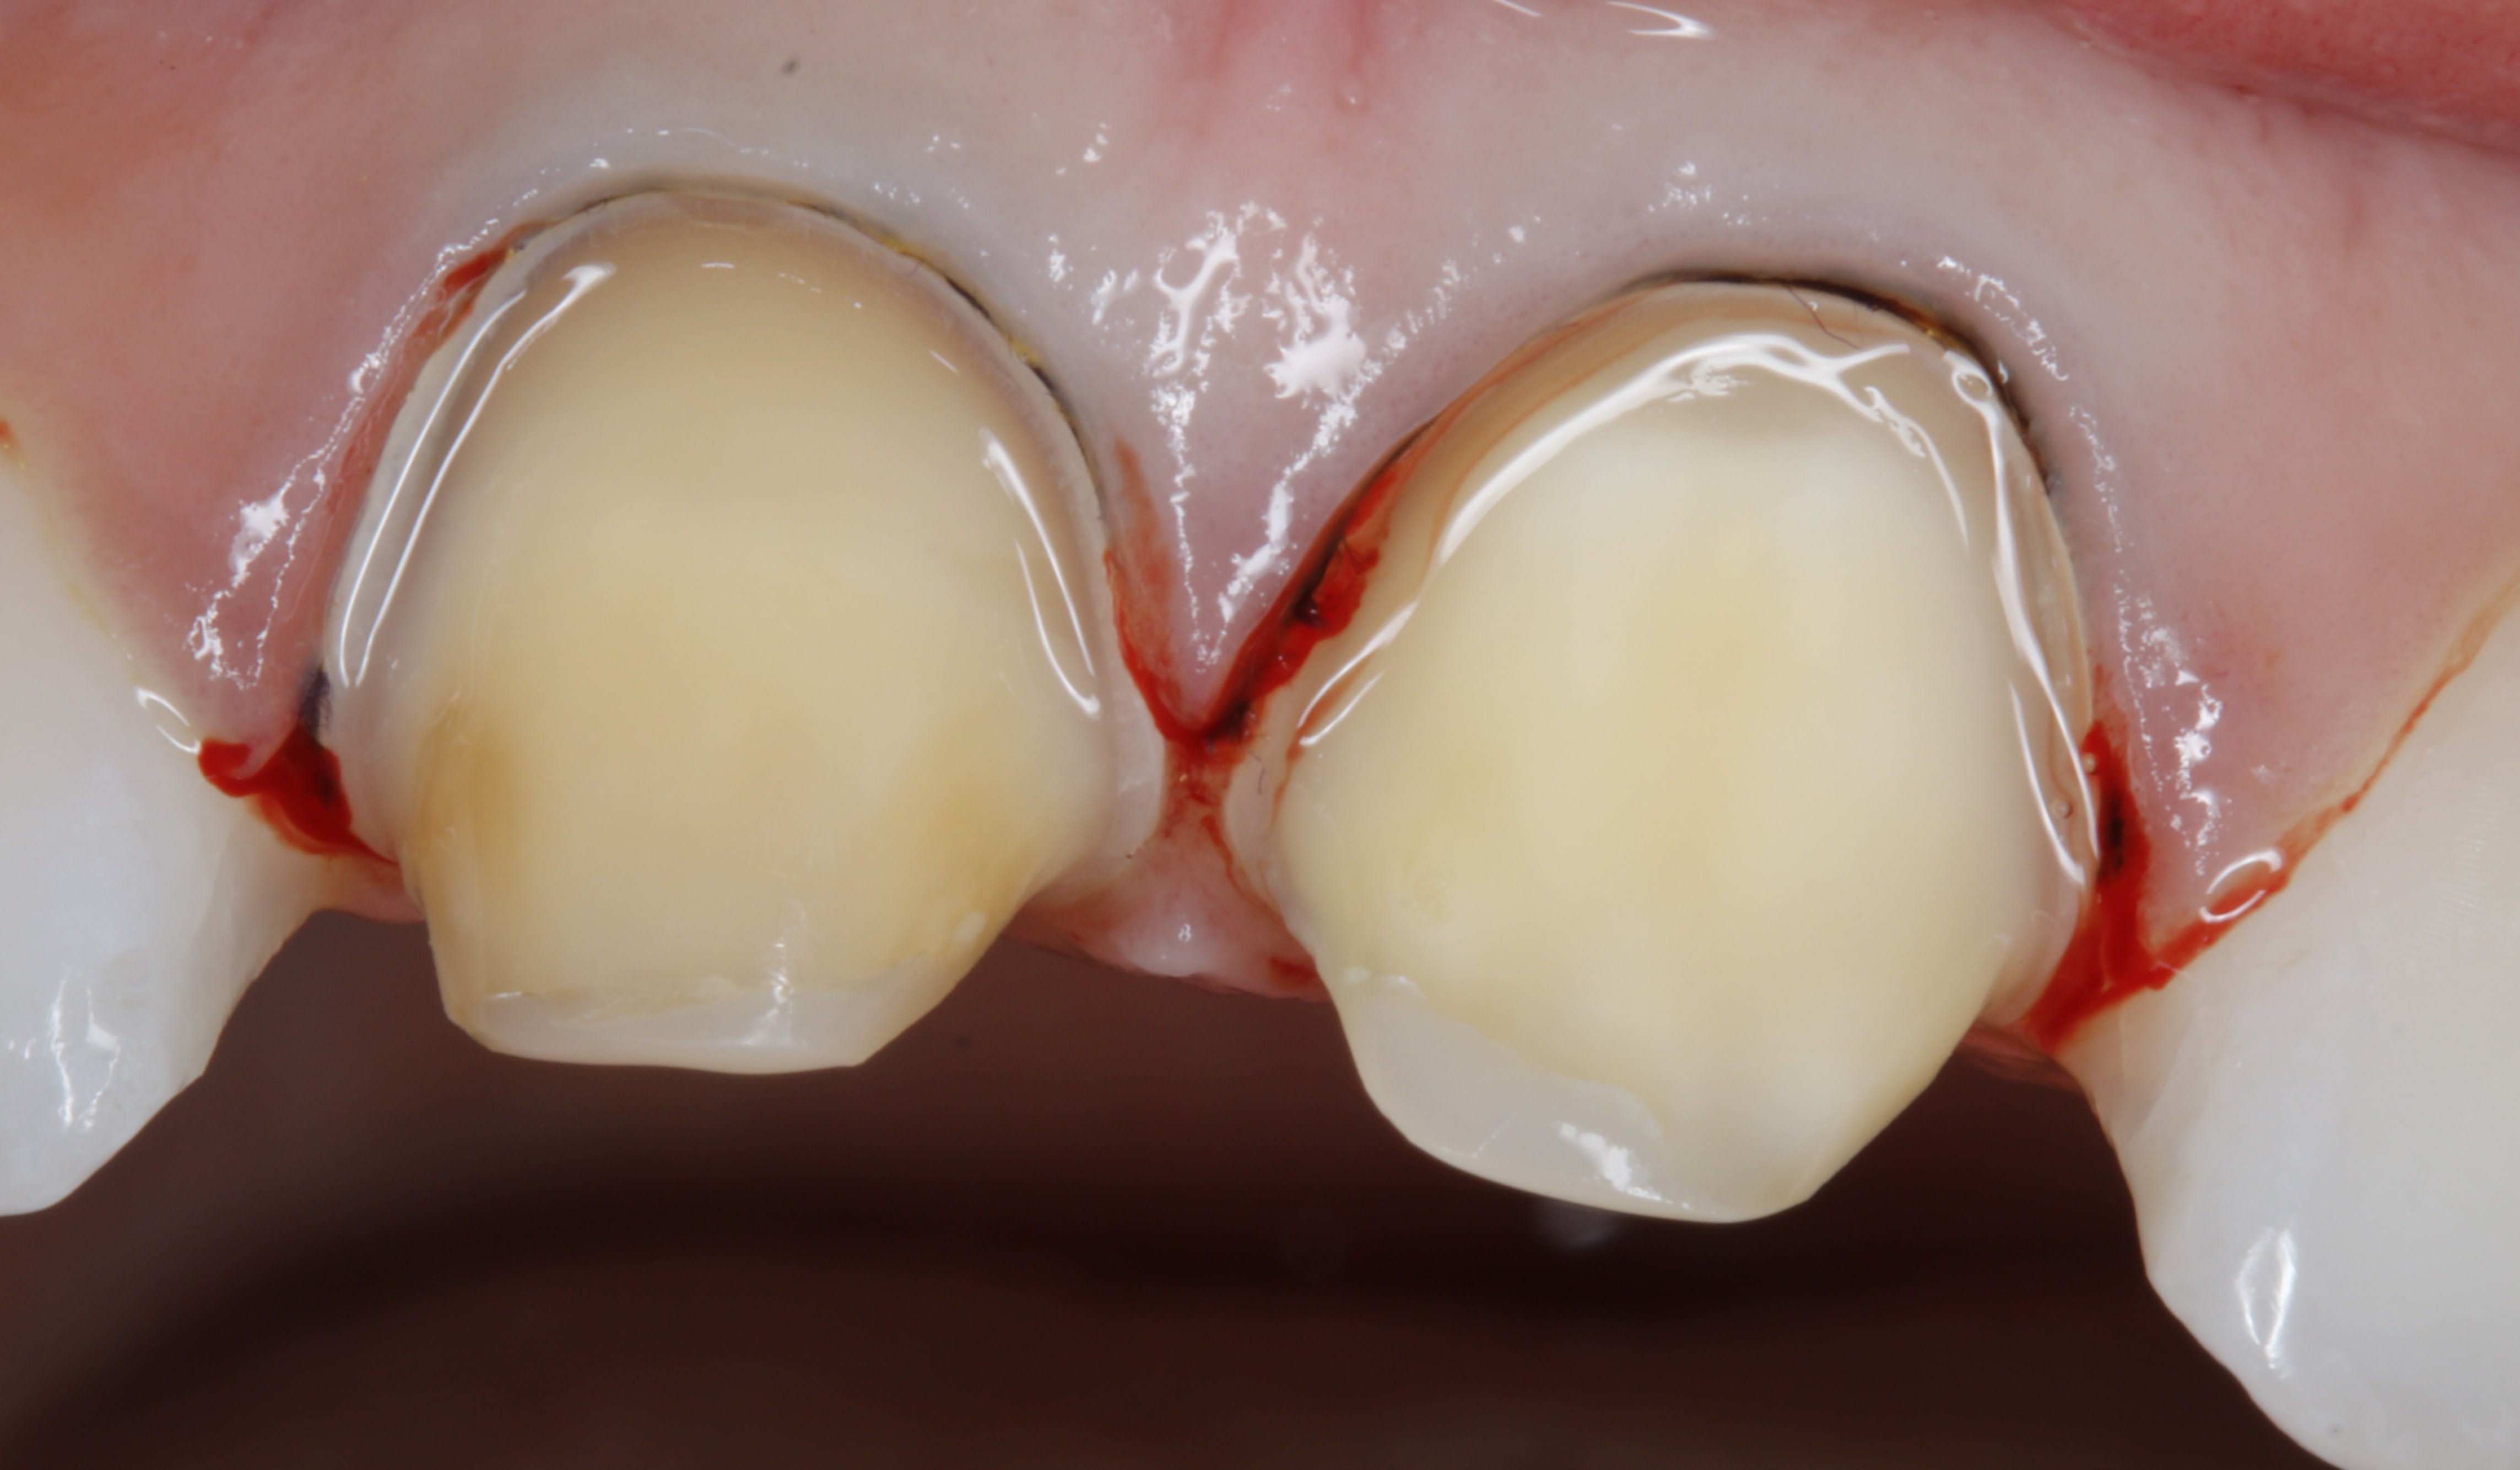

et pourtant ,si on met le fil ,on voit une nette difference entre la limite et le niveau gingival .et pas d'une façon homogène .

ç est cette difference qu'il faut reprendre ,et UNIQUEMENT cette difference .

si tu ne mets pas le fil ,t'y en sais rien .